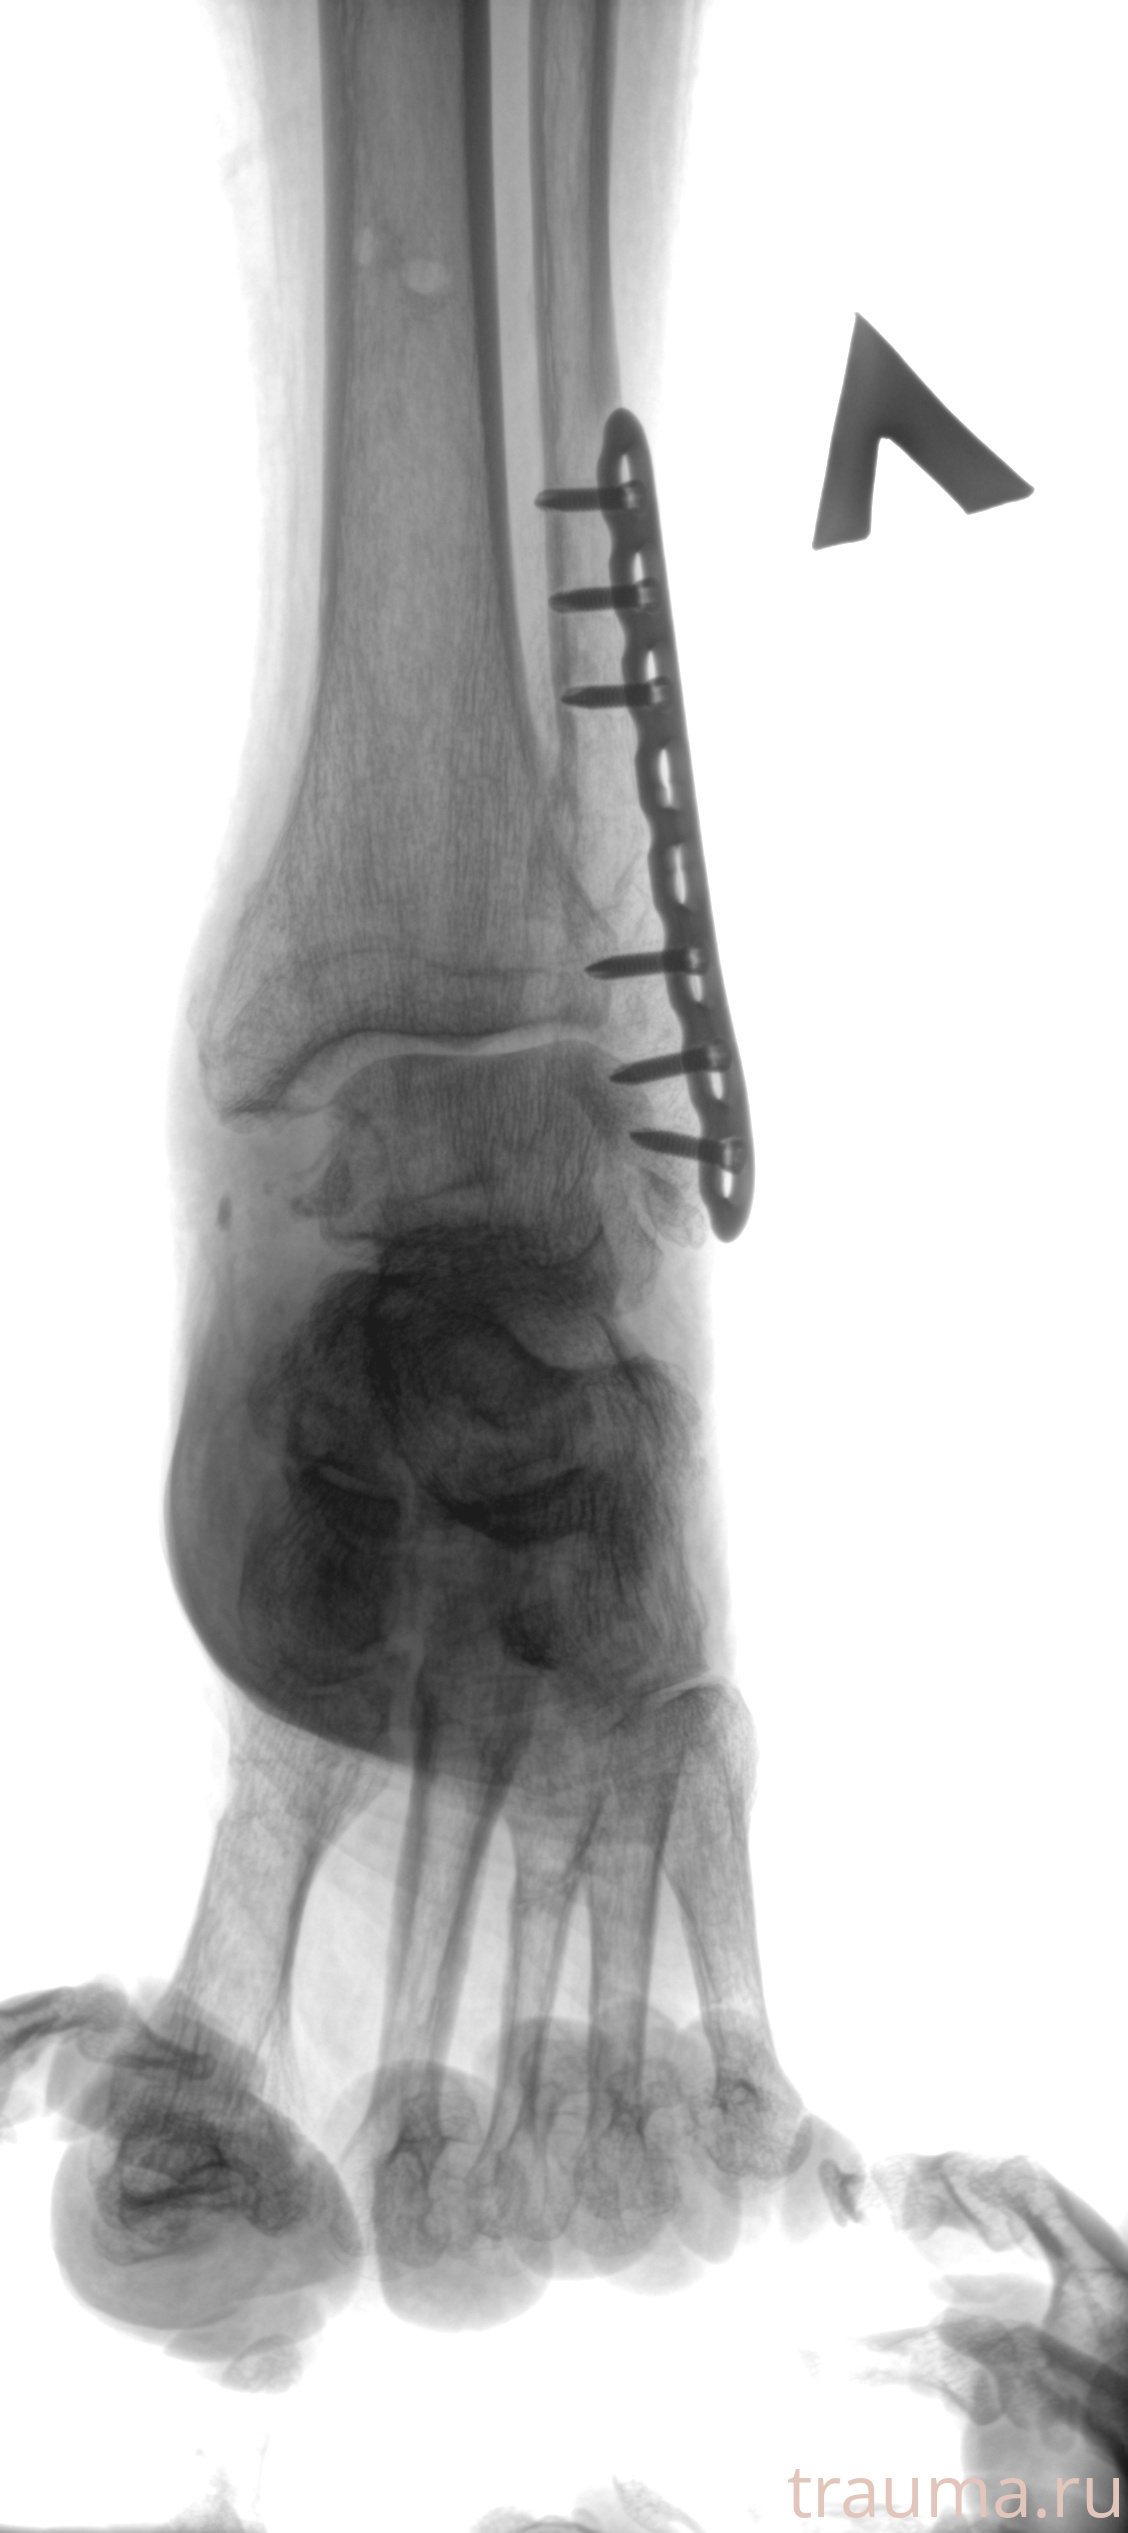

Рентгенограммы